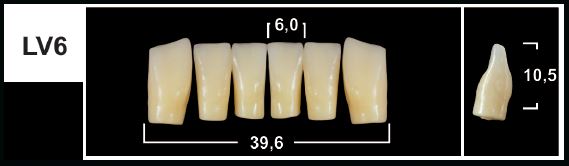

LV6 D4 LOWER ANTERIOR TRIBOS TEETH